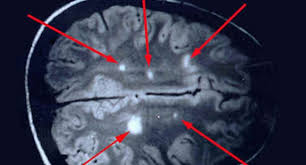

Badanie jest w zupełności bezpieczne. Sclerosis multiplex, sm) jest przewlekłą, autoimmunologiczną chorobą ośrodkowego układu nerwowego.objawia się stopniową degradacją osłonek mielinowych włókien nerwowych, co utrudnia przesyłanie impulsów pomiędzy nerwami. Czasami konieczne jest wykonanie punkcji lędźwiowej. Dwa jasne ogniska po lewej stronie odpowiadają obszarom demielinizacji p.grieb, l.królicki, wpaść w rezonans stwardnienie rozsiane jest jedną z najczęstszych przewlekłych i nieuleczalnych chorób neurologicznych, która na ogół diagnozowana jest między 20. Na stwardnienie rozsiane chorują ludzie do 50 roku życia, potem ryzyko zachorowalności spada. Rezonans magnetyczny głowy oraz kręgosłupa; Na podstawie przedstawionych przez panią danych tj. Diagnoza stwardnienia rozsianego rezonans magnetyczny. Przebieg choroby różni się u każdego człowieka, ale u większości występują okresy zaostrzenia choroby a potem następuje poprawa. U nas, chorych na sm, metoda ta potwierdza obecność ognisk demielinizacji, charakterystycznych dla stwardnienia rozsianego. Stwardnienie rozsiane uznawane jest za najczęstszy czynnik neurologiczny prowadzący do niepełnosprawności u ludzi w młodym wieku. Z przychodni odrazu mi powiedziala ze to stwardnienie rozsiane. Te zmiany chorobowe bywają niekiedy nazywane plakami.

Rezonans magnetyczny pozwala na wykrycie nawet najmniejszych blaszek (płytek) i umożliwia ich odróżnienie od zmian spowodowanych obecnością guza lub uszkodzeniem naczyń krwionośnych, na przykład w wyniku urazu. Że pacjent choruje na stwardnienie rozsiane. U nas, chorych na sm, metoda ta potwierdza obecność ognisk demielinizacji, charakterystycznych dla stwardnienia rozsianego. Przy współpracy z awf wrocław, zapraszamy chorych na stwardnienie rozsiane (sm) oraz osoby po udarze mózgu na cykl zabiegów z wykorzystaniem rezonansu stochastycznego (srt). Głównym badaniem obrazowym, pozwalającym na wykrycie sm, jest rezonans magnetyczny głowy, mózgu oraz rdzenia kręgowego. Stwardnienie rozsiane (sm) a ciąża diagnostyka sm: Tak , podobno stwierdzono , że hormon produkowany na początku ciąży , może być wykorzystany w terapii sm.nawet zaczęto pracować nad stworzeniem leku opratego o ten hormon.ale jeśli wszystko się uda , to będzie on dostępny za dobre parę lat. Badanie jest w zupełności bezpieczne.

Rezonans magnetyczny pozwala na wykrycie nawet najmniejszych blaszek (płytek) i umożliwia ich odróżnienie od zmian spowodowanych obecnością guza lub uszkodzeniem naczyń krwionośnych, na przykład w wyniku urazu.